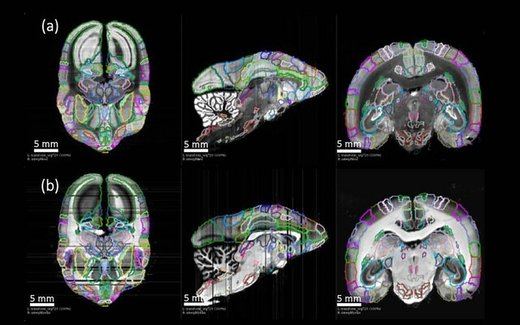

وی با بیان اینکه این مرکز می تواند در سطح ملی و در سطح کشورهای منطقه فعالیت داشته باشد، افزود: در این مرکز می توان امکانات و تجهیزات لازم را برای انجام امور پژوهشی بین رشته ای همچون نقشه برداری مغز نخستیسانان و مطالعه این حیوانات فراهم کرد و این امکانات را در اختیار مراکز تخصصی و فوق تخصصی قرار داد.